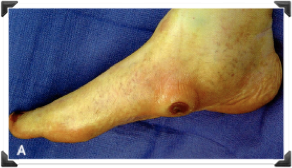

Pie de Riesgo Mecánico en Diabético

Úlcera Neuropática Crónica

2 Sem. Post-Op. - 9 Sem. Post-Op.

Seguimiento a Largo Plazo

5 Años de Post-Operatorio

5 años Úlcera Plantar Recidivante

Pie de Riesgo Rígido Estructurado

Dr. Luis Villanueva

3 Semanas de Post-Operatorio

Dr. Luis Villanueva

Ulcera Neuropatica

3 semanas de Post-Operatorio

Don Humberto

- Edad: 84 años

- Antecedentes: Diabetes Mellitus

- Padecimiento Actual: Dolor, Deformidad, Limitación Funcional

- Ulceras Neuropaticas CRONICAS En Ambos Pies

- Onicomicos Cronica en Ambos Pies

- deformidades mayores

- Tratamiento Podologico Cronico , Peloteo Quirúrgico

Fotos Clínicas

IZQ - DER